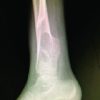

We present a case of SND of the right fourth finger in a 61-year-old female who had undergone an A1 pulley release at an outside facility and presented for evaluation of a right 4th digit swan-neck deformity (Fig. 2a-c).

The patient had a right-hand carpal tunnel release and a 4th and 5th trigger finger release done 9 months prior at an outside hospital. She was approximately 2 months into her post-operative physical therapy when she first noticed swan necking off her 4th digit. She presented to her original surgeon at the outside medical center, who recommended continued observation. She subsequently completed her physical therapy and was given a metal double-ring splint, which she wore for approximately 2 weeks before discarding. She presented to our facility 9 months after the initial surgery as a referral from her primary care physician. She denied any numbness, tingling, or weakness at that time. Her medical history included a history of deep vein thrombosis. Her past surgical history included bilateral carpal tunnel release, open reduction internal fixation of a left distal radius fracture, as well as radical tenosynovectomy and first compartment release of the right first dorsal compartment. The patient stated that she drank alcohol occasionally but denied any history of smoking or drug use. Physical examination revealed a right-hand swan-neck deformity of the 4th digit with 5° of flexion contracture of the MCP joint, 10° extension at the PIP, and 5–10° of flexion contracture at the DIP joint. These findings were all passively correctable, and pressure of the A2 pulley region also passively corrected the deformity. In addition, the patient was able to flex and extend the digit actively. However, the patient could not make a full fist and had a tip-to-palm distance of approximately 1 cm of the ring finger. Due to the previous A1 pulley release, our suspicion was raised for possible extension into the A2 pulley. Therefore, an MRI was ordered to evaluate further. The MRI results revealed that the A2 pulley had been disrupted, with bowstringing of the flexor tendons and an increase in the distance between the flexor tendons and the proximal phalanx and metacarpal. The resulting flexion of the MCP resulted in a stepwise progression to SND of the right 4th finger with no acute fracture or dislocation (Fig. 3).